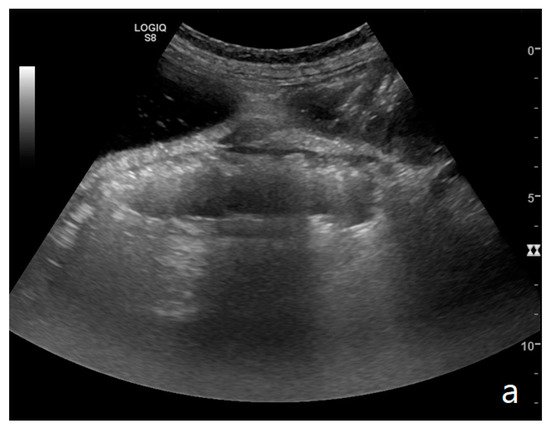

Parietal changes are characterized by the presence or absence of parietal and valvulae conniventes thickening and parietal wall stratification. The evaluation of parietal changes follows a dichotomic diagnostic process based on the reference values (normal thickness 1–3 mm, wall thickening >3 mm, thinned walls <1 mm): thickened walls/valvulae conniventes (YES/NO) or thinned walls (YES/NO) [11][12][3]. Although ultrasound allows us to identify the five concentric layers of the intestinal loops, this evaluation is not applied in the diagnosis of SBO. In practice, the evaluation is limited to the presence or absence of parietal stratification (two-layer double halo sign or three-layer target sign) (Figure 4a–d and Figure 5a,b) [11][3][13].

Figure 5. A complicated SBO presenting fluid-filled bowel loops with thickened walls with a stratified echo pattern (a) and thickened valvulae conniventes (b). Free fluid in the abdominal cavity was detected (b). Tail comet artifacts for air-fluid levels are visible (a). At the time of surgery, the bowel loop was necrotic.

The valvulae conniventes (Kerckring valves, circular folds) are permanent folds composed of mucosa and submucosa that project into the intestinal lumen and are clearly visible in the case of fluid distension (keyboard sign) [5]. At an early stage of SBO, it is not uncommon to see the valvulae in the upstream loop appearing more numerous and closer to each other. As the occlusive state continues, the loop upstream of the obstructive fulcrum becomes weaker, bowel walls appear thin, and the folds flatte. The upstream loops more distant from the obstructive fulcrum may still present peristalsis, albeit reduced and ineffective. In complicated ileus, with the onset of vascular loop distress, the walls and valvulae become thicker and weaker due to parietal edema and venous stasis, with possible dramatic parietal necrosis and subsequent perforation (Figure 4a–d and Figure 5a,b) [2][14].